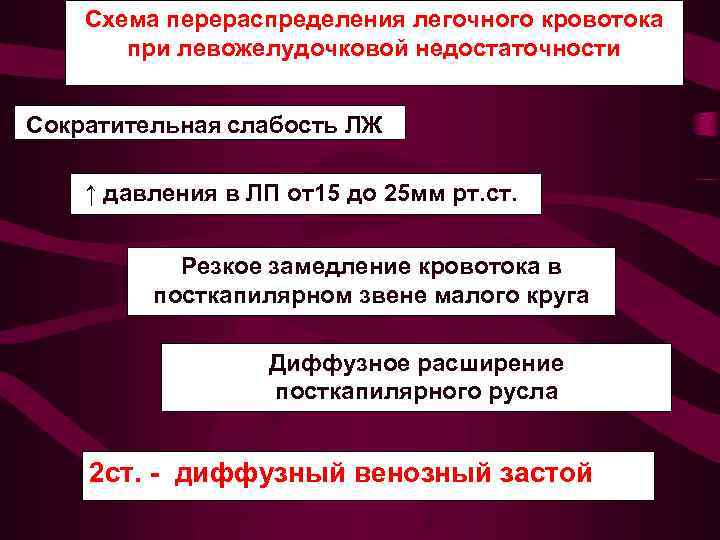

Схема перераспределения легочного кровотока при левожелудочковой недостаточности Сократительная слабость ЛЖ ↑ давления в ЛП от15 до 25 мм рт. ст. Резкое замедление кровотока в посткапилярном звене малого круга Диффузное расширение посткапилярного русла 2 ст. - диффузный венозный застой

Схема перераспределения легочного кровотока при левожелудочковой недостаточности Сократительная слабость ЛЖ ↑ давления в ЛП от15 до 25 мм рт. ст. Резкое замедление кровотока в посткапилярном звене малого круга Диффузное расширение посткапилярного русла 2 ст. - диффузный венозный застой

2 - диффузный венозный застой Среднее давление в левом предсердии от 15 до 25 мм рт. ст. Усилен венозный легочный рисунок во всех отделах легких до перифирии. Увеличено количество сосудистых теней на единицу площади легочного поля. Корни легких расширены структура их не диффе ренцируется. Отмечается нерезкость контуров корня и сосудов.

2 - диффузный венозный застой Среднее давление в левом предсердии от 15 до 25 мм рт. ст. Усилен венозный легочный рисунок во всех отделах легких до перифирии. Увеличено количество сосудистых теней на единицу площади легочного поля. Корни легких расширены структура их не диффе ренцируется. Отмечается нерезкость контуров корня и сосудов.